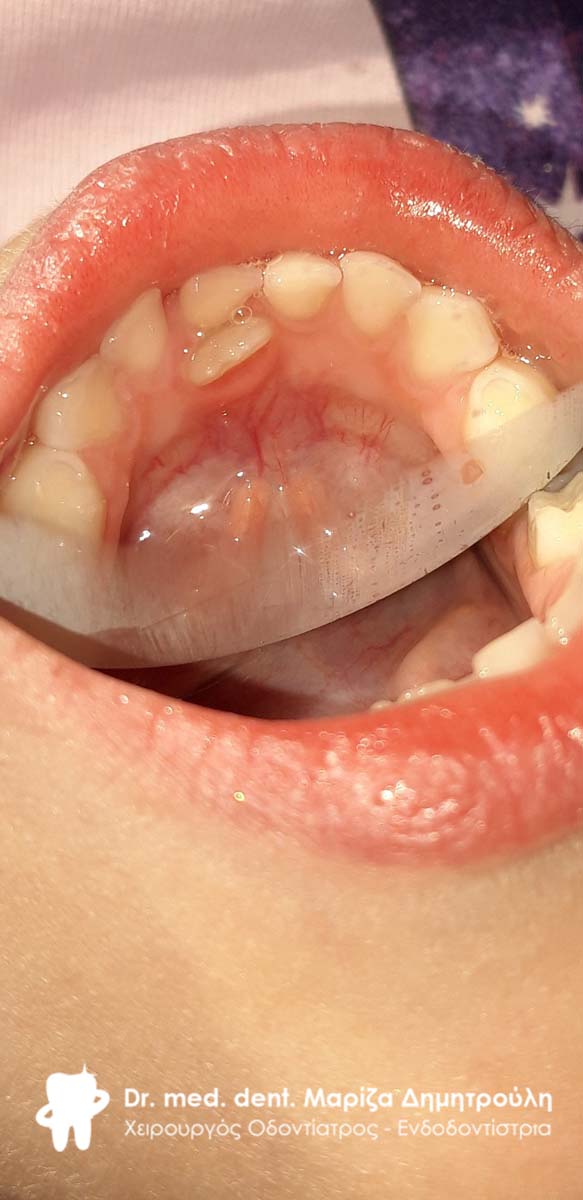

BEFORE

Extraction of double primary tooth